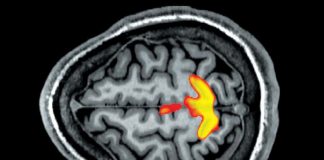

Bolile psihosomatice sau cum psihicul ne poate crea suferințe fizice

Psihicul are un rol foarte important în perceperea și trăirea unei boli. Depresia, anxietatea, conflictele personale, familiale etc., pot da naștere anumitor suferințe cu...